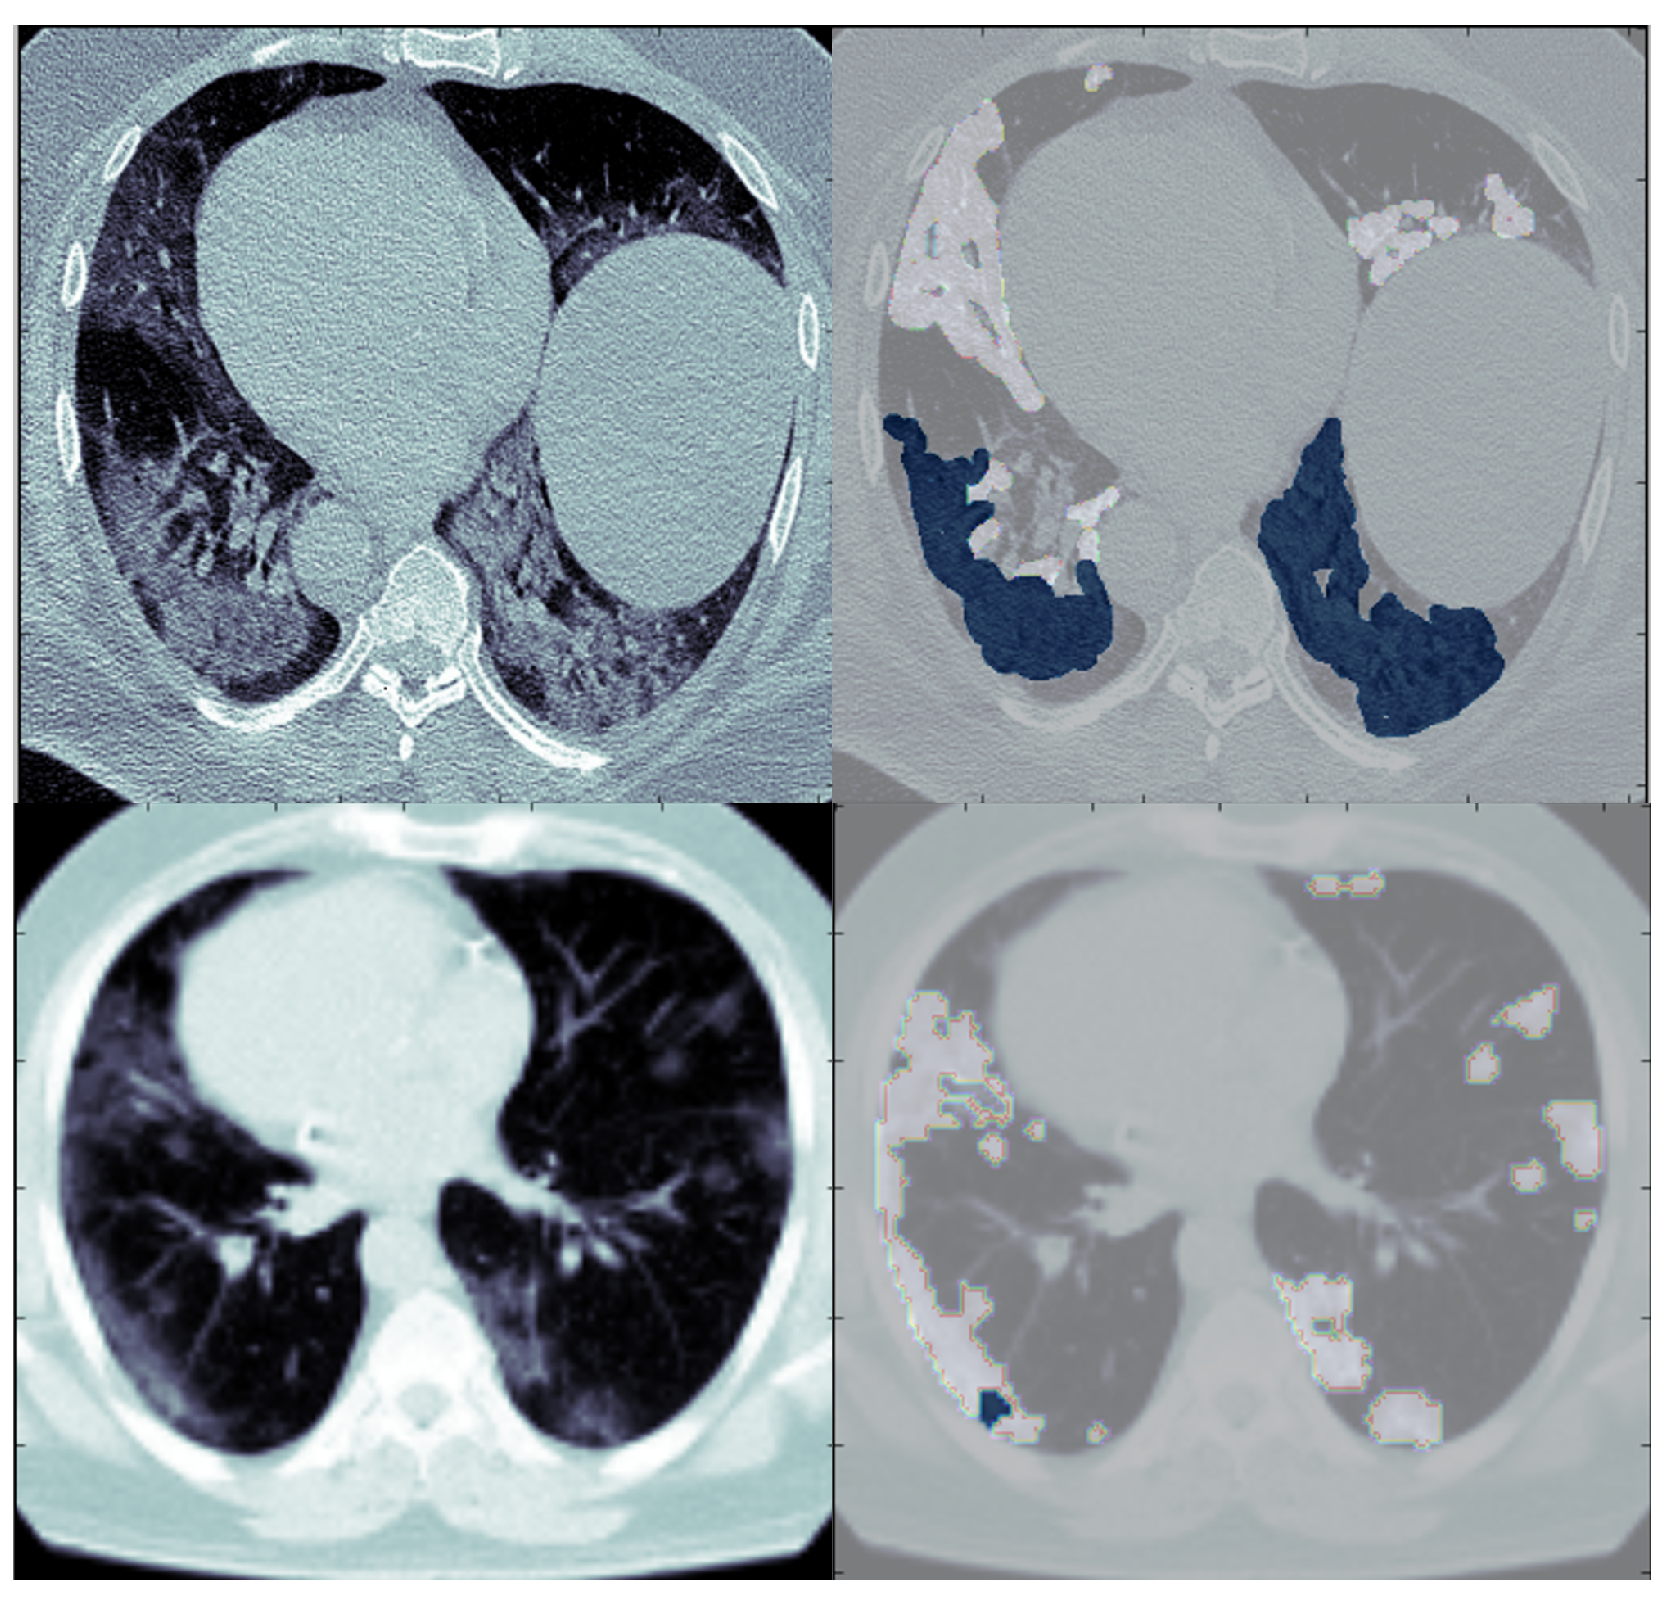

Figure 9.

The predicted CT slices of the best fold for each dataset in binary segmentation. The blue color is for infection, and the others are for the background.

Figure 11 illustrates that the SAA-UNet model can predict different sizes and shapes of the infection. Likewise, SAA-UNet can detect if there is no infection in the CT slices with a mean Dice score of 0.99. As a result, SAA-UNet can diagnose and detect the infection effectively even at the beginning of the appearance of pneumonia in the patient’s lung.

Figure 11.

The predicted CT slices for COVID-19 infection with different sizes. The blue color is for infection, and the others are for the background.